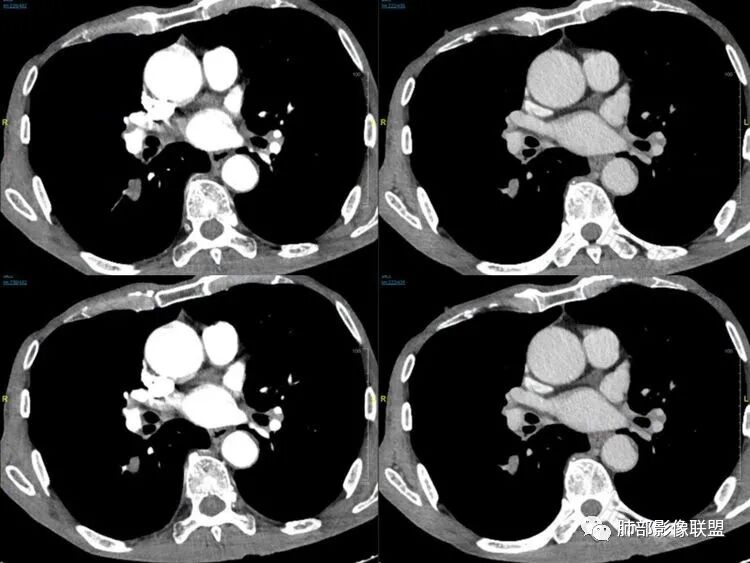

呈典型管状改变,近端支气管堵塞、稍扩张,病灶有强化倾向于恶性,没有强化倾向于炎性病变(结核之类);近端呈结节状(鳞癌多一些),这个病例呈管状(小细胞Ca多一些);平扫与强化有差异,有轻度强化,是粘液栓还是血管?

2娘小崽大、淋巴及血行转移早、冰冻纵隔及肺门、血管脂肪间隙消失

因为病灶侵袭力强,病灶易沿淋巴道、间质及心血管间隙等结构侵犯并密切挤压上述结构,常常能够观察到脂肪间隙消失。易于出现冰冻纵隔。原发灶与肺门转移灶可形成哑铃状外观,甚至转移灶体积大于周围原发灶,有人称之为“娘小崽大”。早期病灶有时很小甚或隐匿,仅能看到转移灶,或转移淋巴结与原发灶融合分界不清。病变向肺门延续的串珠样淋巴结转移也是SCLC的典型特点。

血管包埋征

病灶侵袭力强大,早期沿粘膜下疏松结缔组织及血管旁间隙扩散,包绕血管,血管会受压变形,因为小细胞癌破坏力弱,血管没有被破坏,所以仅仅表现为包埋浸润,但血流面光滑。

乏血供,沼泽样坏死

、罕见空洞

病灶肿瘤密集而供血血管相对不多,密度较均匀,轻度强化,呈乏血供,有时候可以坏死,坏死不彻底,坏死区分散而较小,呈沼泽样坏死,很难造成引流支气管的破坏,所以空洞罕见。